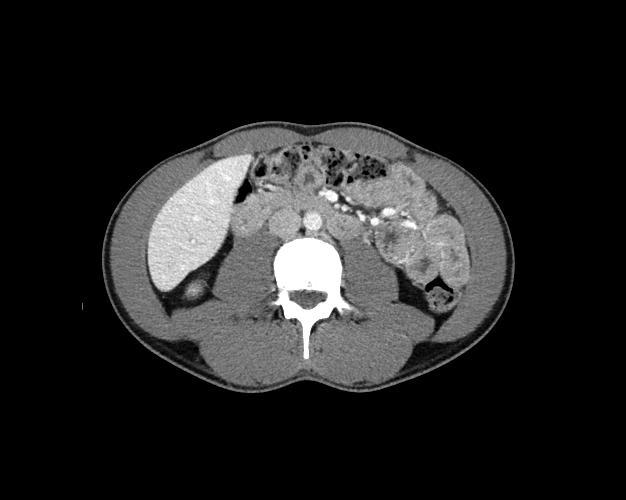

Body

Covers abdominal CT anatomy.